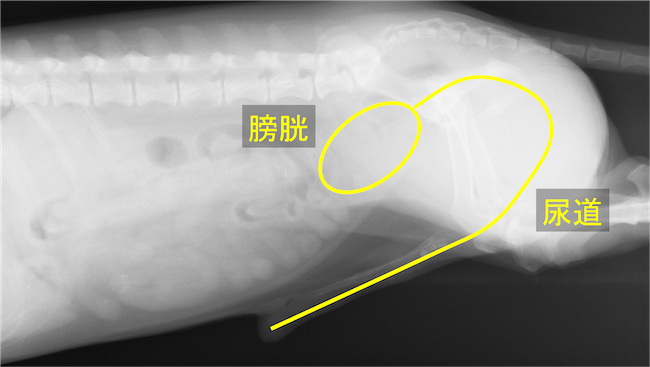

膀胱と尿道の位置

尿道内に結石が5つ連なって認められる

非神経性の原因としては尿道結石や腫瘍、炎症などによって尿道が詰まってしまうことで排尿が長時間できず、膀胱を収縮させる筋肉が壊れてしまうことにより発生します。